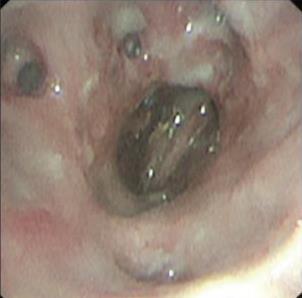

• 侵袭性肺真菌病的支气管镜表现及介入治疗效果

2025, 31(9):81-90. DOI: 10.12235/E20250317

摘要 (112) HTML (56) PDF 6.06 M (77) 评论 (0) 收藏

摘要:目的 探讨侵袭性肺真菌病(IPFD)的支气管镜表现,并评估介入治疗的安全性和疗效。方法 回顾性分析2018年5月12日-2025年5月12日于该院行支气管镜检查的35例IPFD患者的临床资料,观察IPFD的支气管镜表现及介入治疗效果。结果 共收集35例患者临床资料。其中,男22例,女13例,患者年龄(53±14)岁。基础疾病包括:血液系统恶性肿瘤10例,长期应用糖皮质激素者5例,2型糖尿病者4例,肺部恶性肿瘤2例,器官移植1例。胸部CT显示:肺部病变累及单肺叶者19例,累及多肺叶者16例。支气管镜下表现主要为:黏膜充血水肿29例(82.9%)、坏死物堵塞管腔22例(62.9%)、大量黏稠脓性分泌物17例(48.6%)、支气管部分狭窄或闭塞16例(45.7%)、黏膜坏死9例(25.7%)、黏膜出血5例(14.3%)、真菌球3例(8.6%)。其中,32例(91.4%)接受全身性抗真菌治疗,17例(48.6%)接受支气管镜局部两性霉素B灌注治疗,10例(28.6%)采用活检钳钳除病灶,6例(17.1%)采用冷冻探头冻取病灶,4例(11.4%)接受氩气刀治疗。28例(80.0%)临床症状明显改善,肺部影像学病灶缩小或消退;4例(11.4%)病灶稳定;3例(8.6%)未完成治疗。结论 IPFD多见于免疫抑制宿主,支气管镜常表现为:坏死物堵塞管腔、伴脓性分泌物、支气管管腔狭窄和局部黏膜充血水肿或坏死。全身抗真菌药物联合支气管镜下介入治疗,安全性高,且疗效好。